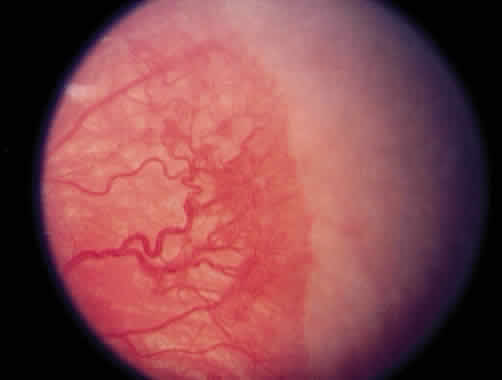

Progressive vascular incompetence, occurring with the changes at the edge of the abnormally developing retinal vasculature, is noted by increasing dilation and tortuosity of the peripheral retinal vessels, iris vascular engorgement, pupillary rigidity, and vitreous haze. When the vascular changes are so marked that the posterior veins are enlarged and the arterioles are tortuous, a plus sign is added to the ROP stage number (Fig. 4). Subsequent to the initial ICROP report, completion of the classification of ROP led to the publication of the classification of retinal detachment.41 Stage 4 was expanded to stage 4A and 4B. Stage 4A (Fig. 5) represents extrafoveal retinal detachment, which is a concave traction type of retinal detachment in the periphery without involvement of the macula. These detachments generally are located in anterior zone II or III. Stage 4B (Fig. 6) is a partial retinal detachment including the fovea, which usually extends in the form of a fold from the disc through zone I to involve zones II and III. Stage 5 retinal detachments are total and always funnel shaped. Stage 5 is subdivided based on the shape of the funnel. The funnel is divided into anterior and posterior parts, allowing for four subdivisions, depending on whether the funnel is open or narrow in both parts of the funnel.

Fig. 6. Stage 4B retinopathy of prematurity.